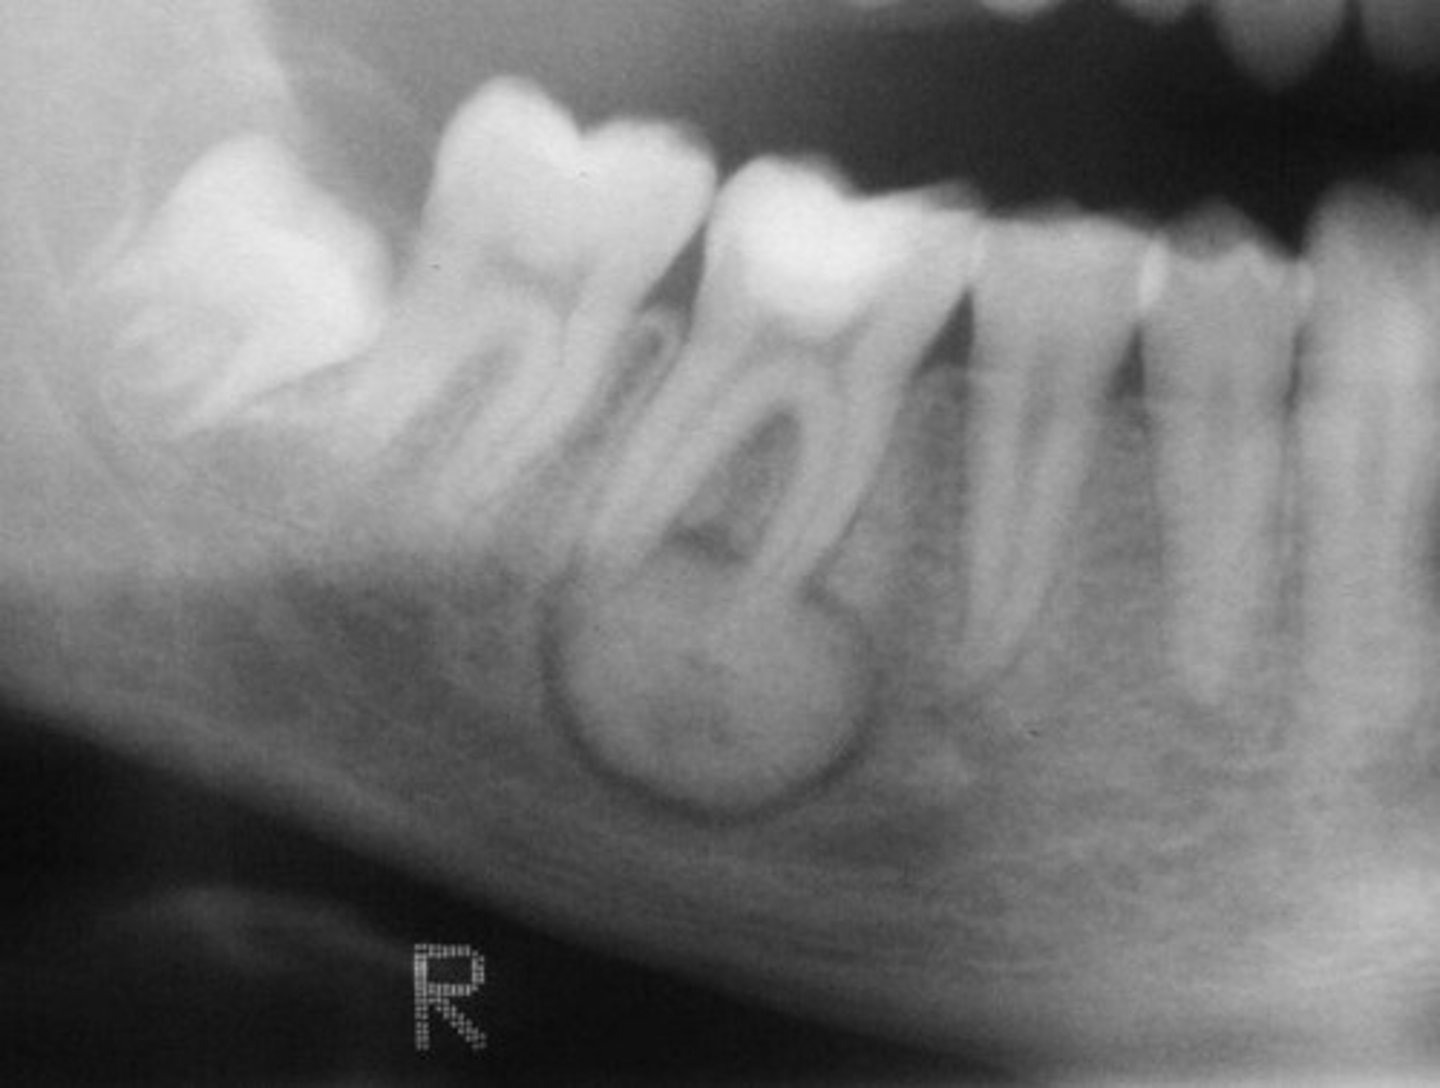

pericoronal

around crown of unerupted tooth

what is this?

what is this radiolucent area in the image?